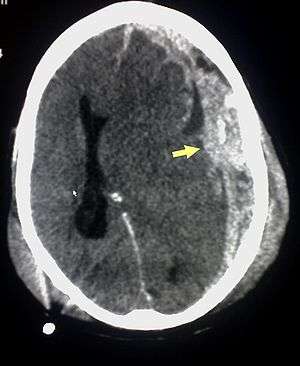

Subdural hematoma (arrow), bleeding between the dura mater of the meninges and the brain, commonly occurs in abusive head trauma | |

Abusive head trauma (AHT), also known as shaken baby syndrome (SBS), is a constellation of medical findings (often referred to as a "triad"): subdural hematoma, retinal bleeding, and brain swelling which some physicians have used to infer child abuse caused by violent shaking. In a majority of cases there is no visible sign of external injury. It is a subset of the broader form of child abuse.[1] The Centers for Disease Control and Prevention identifies SBS as "an injury to the skull or intracranial contents of an infant or young child (< 5 years of age) due to inflicted blunt impact and/or violent shaking".[2]

Characteristic injuries associated with AHT include retinal bleeds, multiple fractures of the long bones, and subdural hematomas (bleeding in the brain).[7] These signs have evolved through the years as the accepted and recognized signs of child abuse and the shaken baby syndrome. Medical professionals strongly suspect shaking as the cause of injuries when a baby or small child presents with retinal bleed, fractures, soft tissue injuries or subdural hematoma, that cannot be explained by accidental trauma or other medical conditions.[8]

SBS may be misdiagnosed, underdiagnosed, and overdiagnosed,[30] and caregivers may lie or be unaware of the mechanism of injury.[14] Commonly, there are no externally visible signs of the condition.[14] Examination by an experienced ophthalmologist is often critical in diagnosing shaken baby syndrome, as particular forms of ocular bleeding are quite characteristic.[31] Magnetic resonance imaging may also depict retinal bleeds;[32] this may occasionally be useful if an ophthalmologist examination is delayed or unavailable. Conditions that must be ruled out include hydrocephalus, sudden infant death syndrome (SIDS), seizure disorders, and infectious or congenital diseases like meningitis and metabolic disorders.[15][33] CT scanning and magnetic resonance imaging are used to diagnose the condition.[14] Conditions that may accompany SBS include bone fractures, injury to the cervical spine (in the neck), retinal bleeding, cerebral bleed or atrophy, hydrocephalus, and papilledema (swelling of the optic disc).[12]